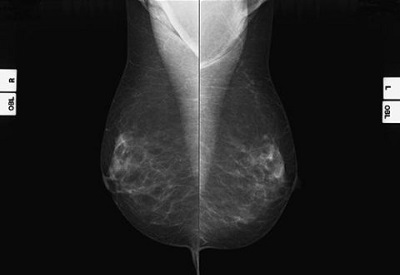

Mammografia. Una conferma della validità dell’indagine

La mammografia ( X-ray a basso dosaggio) è ancora il miglior strumento per lo screening del cancro al seno. LO conferma ancora una volta la…